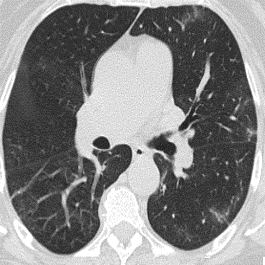

We propose a novel continual self-supervised learning (CSSL) framework for simultaneously learning diverse features from multi-window-obtained chest computed tomography (CT) images and ensuring data privacy. Achieving a robust and highly generalizable model in medical image diagnosis is challenging, mainly because of issues, such as the scarcity of large-scale, accurately annotated datasets and domain shifts inherent to dynamic healthcare environments. Specifically, in chest CT, these domain shifts often arise from differences in window settings, which are optimized for distinct clinical purposes. Previous CSSL frameworks often mitigated domain shift by reusing past data, a typically impractical approach owing to privacy constraints. Our approach addresses these challenges by effectively capturing the relationship between previously learned knowledge and new information across different training stages through continual pretraining on unlabeled images. Specifically, by incorporating a latent replay-based mechanism into CSSL, our method mitigates catastrophic forgetting due to domain shifts during continual pretraining while ensuring data privacy. Additionally, we introduce a feature distillation technique that integrates Wasserstein distance-based knowledge distillation (WKD) and batch-knowledge ensemble (BKE), enhancing the ability of the model to learn meaningful, domain-shift-robust representations. Finally, we validate our approach using chest CT images obtained across two different window settings, demonstrating superior performance compared with other approaches.